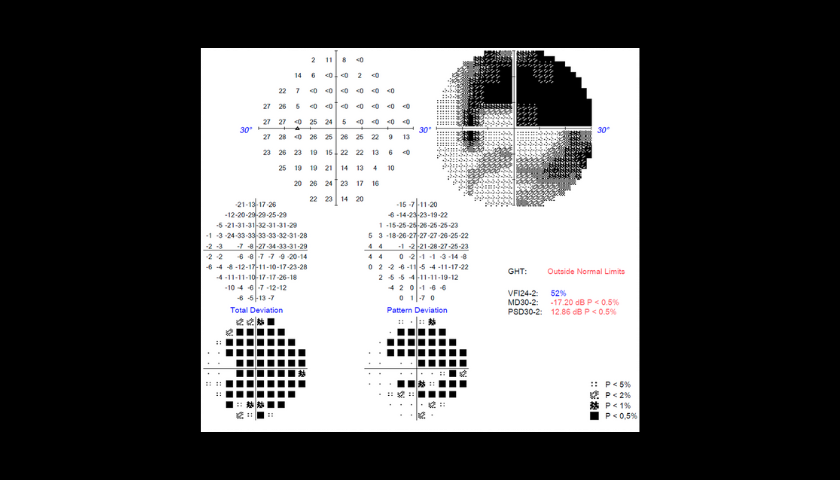

Os colírios são geralmente a primeira linha de tratamento. Pode ser necessário usar mais de um tipo de colírio em simultâneo. É crucial seguir o plano de tratamento porque a falta de uma dose diminuirá o efeito sobre a pressão intraocular, o que poderia levar a uma perda de visão. O doente será aconselhado a fazer controlos regulares para monitorizar a eficácia do tratamento. Durante a visita, o médico pode recomendar que o doente faça um exame OCT ou um Campo VISUAL (PEC) que irá avaliar o estágio da doença e a eficácia do tratamento.